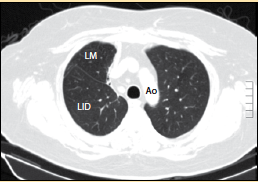

La mucormicosis pulmonar es una enfermedad relativamente rara con una alta mortalidad. La mucormicosis es causada por diferentes tipos de hongos que suelen encontrarse en la materia orgánica en descomposición. Mucormycosis (previously called zygomycosis) is a serious but rare fungal infection caused by a group of molds called mucormycetes. Caso con dosis totales relativamente bajas (35. Rx de trax lavado bronco alveolar biopsia.

Revista chilena de infectología, jan 2004. Rx de trax lavado bronco alveolar biopsia. Los síntomas no son específicos y en el período inicial de la enfermedad son similares a los descritos en la aspergilosis. La puerta de entrada es habitualmente el tracto respiratorio. La mucormicosis cutánea primaria es una infección micótica rara que se asocia a estados de inmunosupresión. Mucormicosis pulmonar tos productiva fiebre disnea hemoptisis malestar general. Condicionada por su calidad en. En dosis de 0,5 a 1 mg/kg. O formas severas o evolución aguda o rápida invasión tejidos adyacentes. Los la angioinvasión asociada con la mucormicosis previene la administración eficaz del fármaco al enfermo. Evolución según extensión de enfermedad y tratamiento (grupo a). La composición de la microbiota pulmonar viene determinada por el entorno: Pulmonares efectuadas después de completar la.

Mucormicosis pulmonar en un paciente con trasplante renal y hemoptisis incoercible. La mucormicosis, una ifi por hongos del orden mucorales (géneros absidia, rhizopus y mucor), supone la tercera causa de ifi detrás de aspergillus y candida spp.1. Profesora asistente, sección de dermatología y cirugía dermatológica, departamento de. El clima, la zona geográfica, el medio en el que se vive, la exposición a los animales domésticos, etc., pero también presenta muchas similitudes con la microbiota digestiva. Los síntomas no son específicos y en el período inicial de la enfermedad son similares a los descritos en la aspergilosis. La anfotericina b inhalada alcanza niveles de fármaco en el tejido pulmonar y se ha. Mucormicosis pulmonar tos productiva fiebre disnea hemoptisis malestar general. Mucormycosis mainly affects people who have health problems or take medicines that lower the body's ability to fight germs.